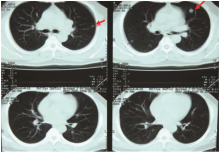

患者男性、51岁, 因“ 涕血3个月” 入院。2010年8月胸部CT检查诊断双肺转移瘤(图1)。2010-09-10我院鼻咽部CT检查示:鼻咽肿物侵犯咽旁间隙、颅底、蝶窦, 伴右颈淋巴结转移(图2); 鼻咽镜行鼻咽肿物活检病理示:鼻咽低分化鳞状细胞癌。诊断为鼻咽低分化鳞状细胞癌cT3N1M1(双肺) Ⅳ c期(AJCC 2010), PS=1。2010-09-21至2011-01-12予TPF方案化疗6周期, 其中紫杉醇256 mg d1、DDP 30 mg d1~d5、5FU 950 mg d1~d5。2周期后(2010-11-04)复查胸部和鼻咽CT示:鼻咽肿物明显缩小, 左上肺前段小结节, 性质待定(图3)。鼻咽部病灶部分缓解(partial remission, PR), 肺部病灶PR, 总评价PR; 4周期后(2010-12-20)复查胸部CT示, 左肺上叶前段纤维灶; 右肺下叶炎性改变, 左肺上叶轻度肺气肿, 肺大泡形成(图4)。4周期后鼻咽病灶PR, 肺部病灶完全缓解(complete remission, CR), 总评价:PR; 6周期后(2011-02-24)复查胸部CT示:双肺多发小结节, 考虑转移瘤可能性大; 肺气肿, 左肺上叶肺大泡形成。鼻咽病灶较前进一步缩小(图5)。6周期后鼻咽病灶PR, 肺部病灶进展(progressive disease, PD), 总评价:PD。

郑登云(肿瘤内科主任医师):该患者从一开始诊断就是一个Ⅳ 期的鼻咽癌, 当时我们按照治疗指南予以TPF方案化疗。4周期后疗效评价, 患者鼻咽部病灶PR, 肺部病灶CR。但化疗6周期后再评价, 患者鼻咽部病灶仍为PR, 而肺部却出现了新的结节。当时结合影像学的结果和我科讨论的意见, 我们认为是肺部出现了新病灶, 病情进展了。此时, CT显示的肺部新病灶, 如何看待, 究竟是否为新发的病灶?下一步该如何治疗?是化疗还是放疗?

张奕(放射科医师):基于患者的病史和外院CT片, 结合该患者2月份到4月份治疗后复查的情况, 因为该患者肺部的转移瘤在缩小中, 4月份的片中瘤灶基本上消失了, 左上肺有一些囊泡状的空泡影, 考虑为肺气肿(图6)。肺内血行转移小结节有以下三方面的特点:①膨胀性生长, 形态比较饱满, ②多呈类圆形, 边缘比较光滑, ③较少侵犯胸膜。根据以上的特点, 我重新回顾了患者2011年2月的CT片, 逐个小结节分析后认为:左下肺的结节是贴着胸膜塌陷式生长的, 形态不太饱满, 边界也不太光滑。右中肺的几个结节的毛刺非常发达(图7), 意识到以前的诊断有些不对。从图中我们可以清晰地看到, 结节不是特别圆, 边缘不光滑, 形态不饱满, 有塌陷, 有些有毛刺。那么这些小结节是否为转移灶?从影像学上来说, 有以下几点支持转移:①多发小结节, ②肿瘤病史; 以下几点不支持转移:①多处病灶位于胸膜处, 并有牵拉征象, ②多处病灶可见长毛刺, ③多处病灶可见塌陷, 形态欠饱满。至此我们认为, 2月份新发病灶的影像诊断应该是炎性肉芽肿。我们的诊断前后不同, 说明我们对病史的了解和图像的观察不够深入。图8是比较典型的炎性肉芽肿(A、B)和转移瘤病灶(C、D)的CT图像。